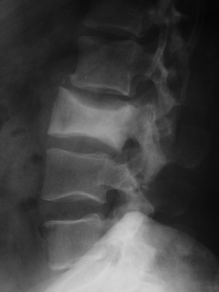

Que tipo de lesão pode ser avaliada através do Rx simples?

lesões ósseas de crânio e coluna, como fraturas e tumores.

Quais os achados radiológicos de metástase óssea?

lesão lítica

reação periosteal em raios de sol

bordas mal definidas

Quais os achados radiológicos da histiocitose de células de Langerhans?

Múltiplas lesões líticas geográficas.

Quais os achados radiológicos da Doença de Paget?

Lesão osteoblástica (maior volume e densidade)

Vértebra com aumento dimensional AP, colapso súpero-inferior, radiopacidade aumentada